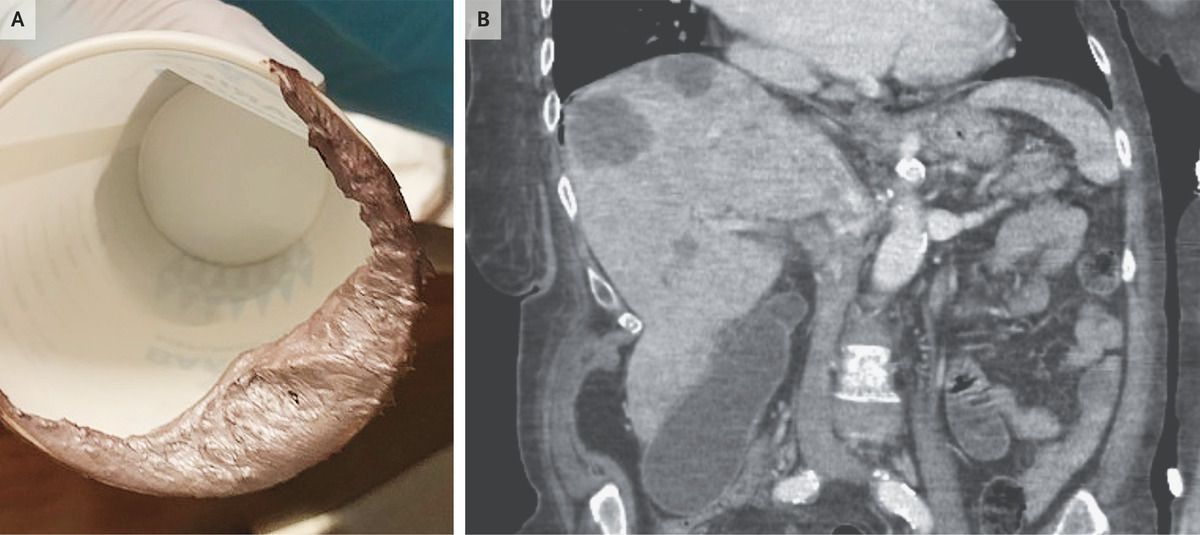

A 69-year-old woman with metastatic colon cancer presented to the emergency department with a 2-week history of dizziness and unusually colored stool. She had no associated itching or darkening of the urine. The physical examination was notable for jaundice, hepatomegaly, and a diffusely tender abdomen. The rectal examination showed silver-colored stool (Panel A). Laboratory studies were notable for a hemoglobin level of 7.5 g per deciliter (reference range, 11.0 to 14.5), a total bilirubin level of 4.0 mg per deciliter (68 μmol per liter) (reference range, 0.2 to 1.3 mg per deciliter [3 to 22 μmol per liter]), and an alkaline phosphatase level of 369 U per liter (reference range, 45 to 117). Testing of the stool was positive for occult blood. Findings on computed tomography of the abdomen and pelvis included a cecal mass and multiple liver metastases (Panel B). The appearance of silver stool results from a combination of white stool associated with obstructive jaundice and black stool of melena. After a discussion of treatment options with the patient, a decision was made to focus on her comfort. She was discharged home with hospice care.